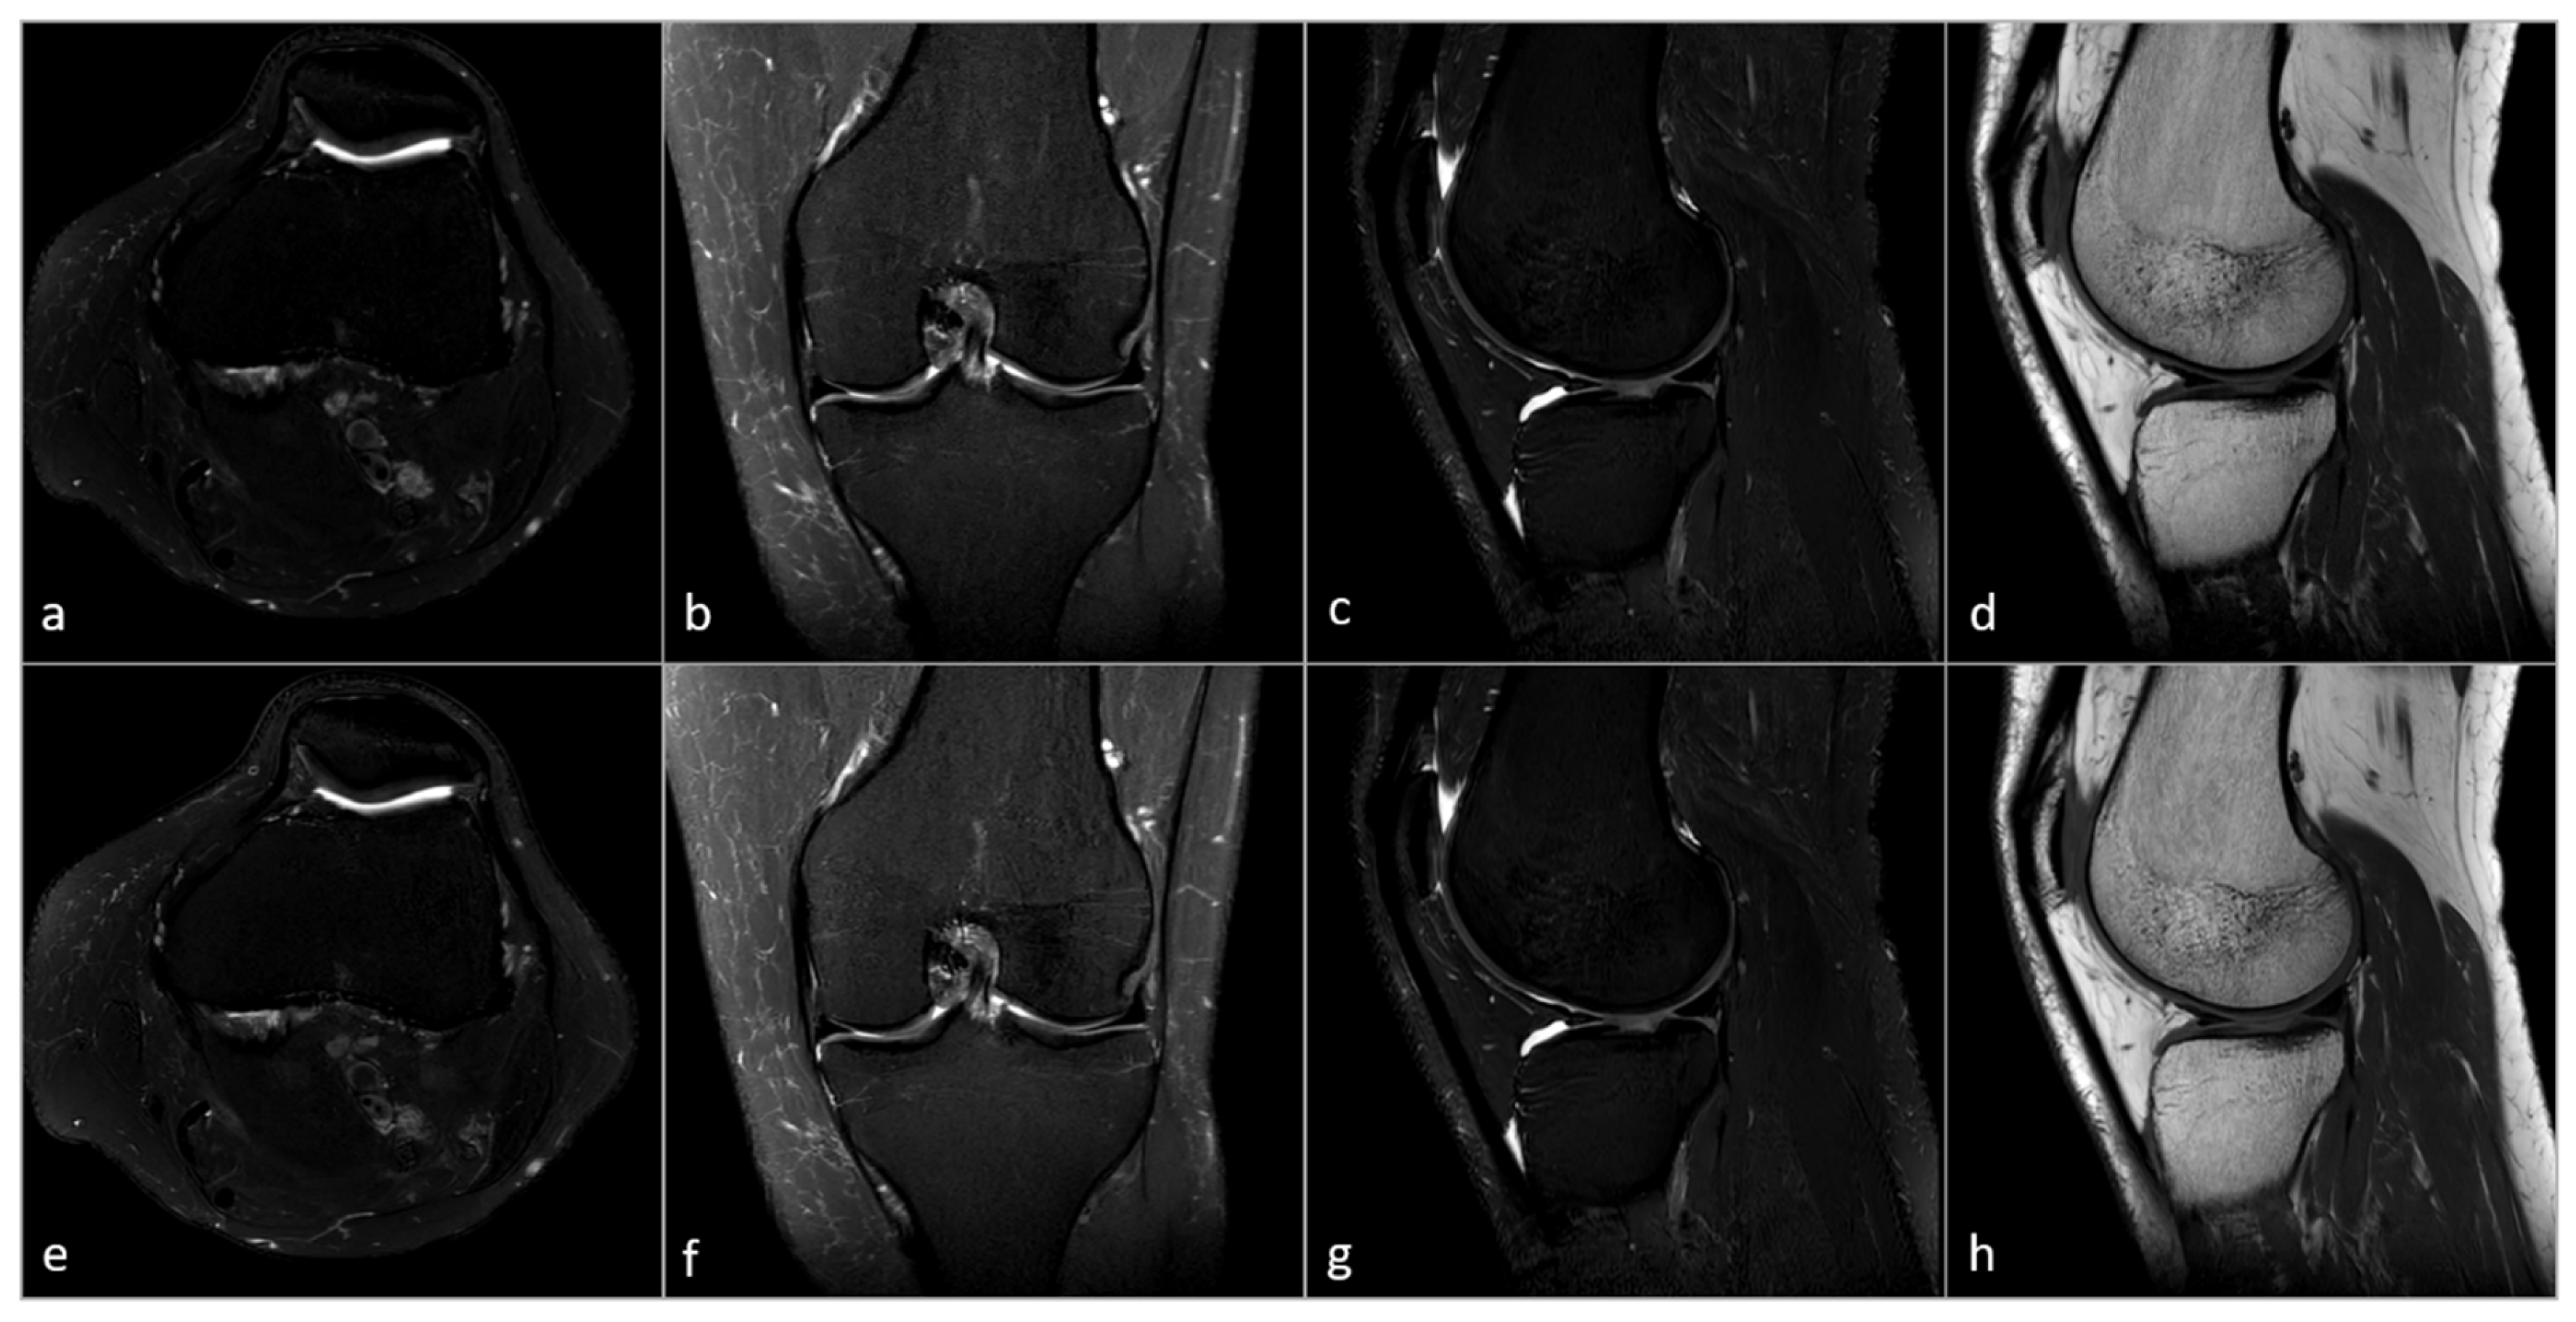

3.3. Subjective Image Analysis

3.4. Objective Image Analysis